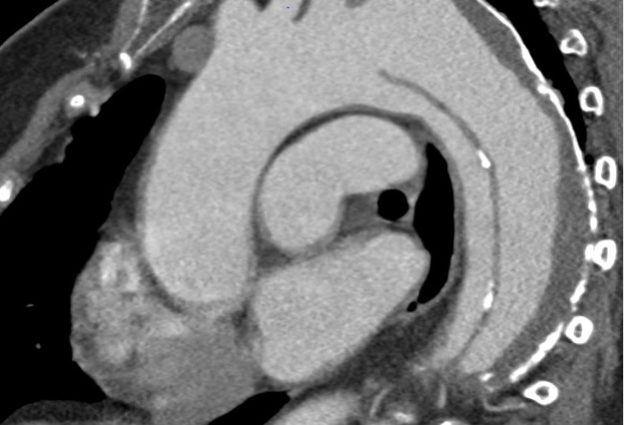

Was genau ist die Aorta und welche Erkrankungen der Aorta werden in der Gefäßchirurgie Siegen behandelt? SIEGEN. Die Aorta ist die Arterie, die von der linken Herzkammer zunächst aufsteigend, dann mit einem Bogen durch den Brustkorb in den Bauchraum verläuft und schließlich in die Beckengefäße übergeht. Von dieser Hauptschlagader hängt die gesamte Versorgung des Körpers…